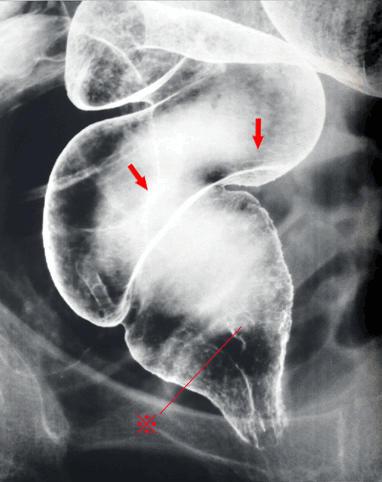

疾病(病理主体)的分类恶性上皮肿瘤/腺扁平上皮癌

部位(按器官分)大肠/直肠

检查方法X线

肿瘤最大直径40以上

肿瘤的深度ss(a1)

多发性肿瘤(同一器官)

多重性肿瘤(多个器官)有(异时性)